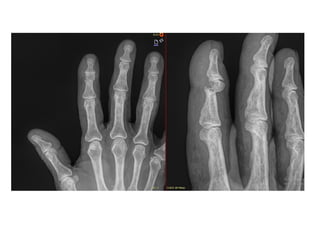

NOMBRE: ROSAS OLMEDO BERENICE

3095620304 / 5F1962PE

URGENCIAS A

Edad: 63 AÑOS

Comorbilidades: DM2

Fecha de la lesión: 18/09/25

Mecanismo de lesión: APLASTAMIENTO CON PUERTA DE 2DO DEDO MANO DERECHA

Laboratorios: DENTRO DE NORMALIDAD

Valoraciones: NA

Diagnósticos: FRACTURA DE FALANGE MEDIA DE SEGUNDO DEDO DE MANO DERECHA

Cirugía Proyectada: REDUCCION CERRADA Y FIJACION PERCUTANEA DE FALANGE MEDIA DE SEGUNDO DEDO DE MANO DERECHA

CON CLAVILLOS K

Material OSS Solicitado: CLAVILLOS K

NOMBRE: APRESA MENDEZ VALERIA

4611930427 / 1F1993OR

Edad: 32 AÑOS

Comorbilidades: NINGUNA

Fecha de la lesión: 14/09/25

Mecanismo de lesión: CONTUSION DIRECTA MANO DERECHA

Diagnósticos: FRACTURA DIAFISARIOA TERCIO DISTAL DE QUINTO METACARPIANO MANO DERECHA

Cirugía Proyectada: REDUCCIÓN ABIERTA Y FIJACIÓN PERCUTÁNEA CON CLAVILLOS K A QUINTO METACARPIANO MANO DERECHA

NOMBRE: ROSAS OLMEDOBERENICE 3095620304 / 5F1962PE URGENCIAS A Edad: 63 AÑOS Comorbilidades: DM2 Fecha de la lesión: 18/09/25 Mecanismo de lesión: APLASTAMIENTO CON PUERTA DE 2DO DEDO MANO DERECHA Laboratorios: DENTRO DE NORMALIDAD Valoraciones: NA Diagnósticos: FRACTURA DE FALANGE MEDIA DE SEGUNDO DEDO DE MANO DERECHA Cirugía Proyectada: REDUCCION CERRADA Y FIJACION PERCUTANEA DE FALANGE MEDIA DE SEGUNDO DEDO DE MANO DERECHA CON CLAVILLOS K Material OSS Solicitado: CLAVILLOS K

NOMBRE: APRESA MENDEZVALERIA 4611930427 / 1F1993OR URGENCIAS A Edad: 32 AÑOS Comorbilidades: NINGUNA Fecha de la lesión: 14/09/25 Mecanismo de lesión: CONTUSION DIRECTA MANO DERECHA Laboratorios: DENTRO DE NORMALIDAD Valoraciones: NA Diagnósticos: FRACTURA DIAFISARIOA TERCIO DISTAL DE QUINTO METACARPIANO MANO DERECHA Cirugía Proyectada: REDUCCIÓN ABIERTA Y FIJACIÓN PERCUTÁNEA CON CLAVILLOS K A QUINTO METACARPIANO MANO DERECHA Material OSS Solicitado: CLAVILLOS K